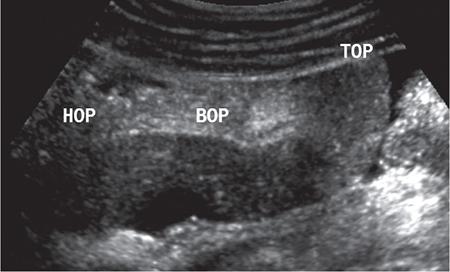

Kajal Patel, L. Murali Krishna Pancreatic transplantation is currently the only effective treatment for type 1 diabetes mellitus (93% of cases) allowing long-term glycaemic control without exogenous insulin injections. Additionally, it also counteracts the complications of diabetes mellitus, including diabetic neuropathy, retinopathy, vasculopathy and end-stage renal failure. The standard procedure is transplantation of a whole-organ cadaveric pancreas but less-invasive approaches such as islet cell transplantation are in development. Simultaneous pancreas–kidney (SPK) transplantation (78%) is done in most of the cases with same donor. In 16% cases, pancreas transplant can be done after kidney transplant also. But rarely, isolated pancreatic transplant (6%) can be done. The first pancreatic transplantation was performed in 1966 by the team of Dr. Kelly, Dr. Lillehei, Dr. Merkel, Dr. Idezuki Y and Dr. Goetz, 3 years after the first kidney transplantation. According to Scientific Registry of the United Network for Organ Sharing (UNOS) and the International Pancreas Transplant Registry (IPTR), the national 1-year patient, kidney and pancreas survival rates for recipients of an SPK transplant are 95%, 89% and 85%, respectively. Pancreas grafts have vascular and enteric connections that vary in their anatomic approach and understanding of this is critical for imaging. Imaging techniques are directed to display the pancreatic transplant arterial and venous vasculature, parenchyma and intestinal drainage pathway. Various surgical techniques have evolved over the years especially in the recent decade. Imaging of these patients should also be done based in the common surgical techniques and complications that arise of these surgeries. Though multiple modalities like ultrasonography (US), computed tomography (CT) and magnetic resonance (MR) imaging, radionuclide study and digital subtraction angiography (DSA) are available, each of them have their own advantages and limitations and usually a multimodality approach is required to diagnose the spectrum of complications. Preoperative evaluation typically considers the potential recipient’s age and ability to survive the operation. A relative contra-indication is the patient’s age (>55 years), due to the fact that the success rate is superior in younger individuals. Key components of the assessment include determining the presence of renal, cardiac, peripheral vascular, cerebro-vascular and psychiatric diseases. The pretransplant work-up consists of extensive laboratory, infectious and physiologic testing. Chest radiography is required for preoperative fitness of recipient. The extent of aorto-iliac calcification of recipients, a factor in choice of implant site, is evaluated with unenhanced CT. Donor factors such as age, sex, body mass index, cause of death, donation after cardiac death, serum creatinine and preservation time (cold ischaemia) can influence the outcome of pancreas transplantation. Usually, evaluation of donor pancreas is best done by the pancreatic transplant surgeon intraoperatively. Visual inspection of pancreas in terms of its size, texture, colour, fibrosis, fatty infiltration and its vascular supply is essential. There is very little role for preoperative imaging in the setting of deceased organ donation. The donor’s pancreas is harvested en bloc with its respective vascular support and a variable duodenal segment that contains the ampulla of Vater. The most common technique consists placing the pancreatic graft intraperitoneally in the right pelvic region with the duodenal segment facing cephalad and the renal graft in the left iliac fossa, extraperitoneally. Whole pancreatic graft transplantation can be performed with a duodenal segment; in this type of transplantation, donor’s duodenum is anastomosed with the recipient’s small bowel loop for enteric exocrine drainage and grafted portal vein is anastomosed with common iliac vein or inferior vena cava for systemic endocrine drainage (Fig. 9.20.1). Another way of restoring the endocrine drainage, grafted portal vein may be anastomosed with the recipient’s portal venous system and for exocrine drainage duodenal segment may be anastomosed with the urinary bladder. Duodenoenterostomy done by side to side anastomosis of donor’s duodenal segment to the recipient’s small bowel loop. Arterial supply is established by using the donor’s aortic patch, containing the splenic artery and the superior mesenteric artery (SMA), which is anastomosed to the recipient’s common or external iliac artery. Native pancreas of patient is left untouched in the upper abdomen. After placement of pancreatic graft by surgeon, pancreatic graft Doppler evaluation should be done intraoperatively. Intraoperative ultrasound probe is directly put on anastomotic artery and vein which show normal colour flow without evidence of thrombosis. In the case of occlusion, there is no evidence of colour flow. In the case of occlusion, surgeon does re-anastomosis of vessels once thrombi are removed. Due to its superficial location in pelvis and visualization of pulsation of vessels, visual inspection is sufficient for patency of vessels. So most of the time intra-operative Doppler study is not necessary. Postoperative imaging of pancreas transplantation is a challenge for the radiologist because of the altered surgical anatomy, identifying the pancreatic graft from adjacent structures and various postoperative complications that may arise posttransplantation. Imaging evaluation of the pancreas transplant grafts is commonly performed by a multitechnique approach. The most commonly utilized scanning techniques include US, CT and MR imaging. DSA and radionuclide study are routinely not performed nowadays. Ultrasound usually represents the first line imaging method in the assessment of the pancreatic graft, due to its portability, repeatability for ill and unstable patients in the immediate postoperative period, lack of ionizing radiation, and it provides a real-time vascular flow map which may allow detection of vascular anastomotic stenosis and reduced pancreatic graft perfusion. Its evaluation may, however, be limited due to the intraperitoneal position of the pancreas graft, in particular with the portal enteric approach with the organ in the right upper abdomen and intestinal gas overlap. Unless abnormally dilated, the duodenal component often cannot be separately evaluated by ultrasound. Additionally, ultrasound may be fundamental in guiding the percutaneous biopsy. Although the lack of an organ capsule generally results in an ill-defined appearance, the pancreatic transplant can be identified by its relatively cylindrical shape. In greyscale B-mode, the normal pancreatic graft presents homogeneous echotexture, lower than the native pancreas and the surrounding mesenteric or epiploic fatty tissue (Fig. 9.20.2). Colour and power Doppler US play a vital role in demonstrating pancreas transplant perfusion and vascular anatomy. We would also be able to visualize the Y arterial graft, graft vein, splenic artery and vein (Fig. 9.20.3A and B). Venous structures demonstrate a monophasic waveform within an anechoic lumen and velocities ranging between 10 and 60 cm/s. Normal arterial waveform exhibits a sharp systolic upstroke and a continuous diastolic flow. In the immediate postoperative period, the velocities of the arterial anastomosis may be very high as 400 cm/s due to possible postoperative oedema and/or due to kinking of the anastomosis. Usually in both the cases, the arterial anastomotic velocities gradually decrease on in follow-up. The resistive index (RI) may be of limited use to diagnose graft rejection, as the values may be as high as 0.9 and are variable throughout the gland. Due to the presence of renal capsule in a transplanted kidney, there is elevated vascular resistance when there is intrarenal oedema; however, due to the absence of capsule in the transplanted pancreas, the vascular resistance will be normal in spite of oedema secondary to pancreatitis or rejection. CT is generally required after an abnormal ultrasound or whenever the patient presents unexplained fever, abdominal pain or when abnormal laboratory data are found. Contrast-enhanced CT helps to evaluate the graft parenchyma, the enteric and vascular anastomosis and in diagnosing postoperative complications such as focal collections, vascular thrombosis or pneumoperitoneum. In noncontrast CT scan, pancreatic graft appears as a homogeneous isodense soft tissue organ. It is more difficult to differentiate between pancreatic graft and nonopacified and nondistended small bowel loop in plain/noncontrast CT scan. But you can always make out the surgical clips which are stapled on duodenal stump, which can be helpful for localization of pancreatic graft. Nonenhanced images should be acquired with the goal of locating the graft and possible early thrombus or haematoma. The protocol used should include (positive) enteric contrast that allows identification of intestinal loops adjacent to the graft and distinction from possible liquid collections (Fig. 9.20.4A). The donor’s duodenum is frequently collapsed and may fill (or not) with the given oral contrast. IV contrast material is administered infrequently, to avoid the risk of nephrotoxicity, if native renal function is impaired. About 120–150 mL of contrast medium greater than 350 mg iodine per millilitre is injected at the rate of 4–6 mL/s. Late arterial phase can be obtained with the bolus-tracking technique located in the common iliac artery (attenuation value of 150 HU) and is very useful in the assessment of parenchymal enhancement and arterial anastomosis; 50 seconds after the administration of intravenous contrast material, the portal venous phase evaluates the respective drainage and possible associated venous complications (Fig. 9.20.4B). CT images are evaluated by axial, multiplanar reformats and three-dimensional maximum intensity projection (MIP) and volume-rendered techniques. The normal pancreatic parenchyma will enhance uniformly more in the arterial phase than in the venous phase. The iliac arterial graft, peripancreatic and intrapancreatic arterial vasculature, as well as the anastomosis of the donor portal vein to the recipient iliac or superior mesenteric vein, should be delineated. Coronal reformats are the best to illustrate the intestinal anastomosis and to determine if the graft is placed inferiorly for a systemic venous drainage or superiorly for a portal venous drainage. MR is usually indicated in young patients in which cumulative radiation is an essential consideration. Contrast-enhanced MR angiography is used for evaluating the arterial and venous anatomy of pancreatic graft; however, it is difficult to access the enteric anastomosis and postoperative complications due to low spatial resolution. Also, it is a challenge to image sick patients requiring intense monitoring and those with metallic clips. An appropriate protocol includes axial T1-weighted (T1WI) (precontrast; in-phase and out-of-phase), coronal T2-weighted (T2WI) fast-spin-echo and axial T2-weighted fat-suppressed sequences. Furthermore, images after intravenous contrast administration (gadolinium-based) should be acquired in arterial and venous phases. Unenhanced MR imaging readily helps distinguish the pancreatic allograft from adjacent structures and is superior to CT without intravenous contrast material. In plain MRI of abdomen, pancreatic graft appears hyperintense as compared to liver and appears as homogenous structure on T1-weighted images. Normal pancreatic graft’s signal intensity is between that of fluid and muscle on T2-weighted images. Various pathologic process of graft pancreas is more related to increased glandular water content, so T2-weighted images are more sensitive to diagnose graft pathology (Fig. 9.20.5A). Axial and coronal images are useful in displaying pancreatic and peripancreatic graft oedema, as occurs in pancreatitis, and in characterizing peritransplant fluid collections (haematoma/seroma). The MR angiography helps to access the arterial and venous anatomy and can diagnose arterial or venous stenosis and venous thrombosis. The normal pancreas graft enhances briskly and homogeneously in the late arterial phase (Fig. 9.20.5B). Gadolinium-based contrast agents may pose the risk of nephrogenic systemic fibrosis in selected patients with advanced renal dysfunction. The normal pancreatic duct is generally not visible with US or CT but may be observed as a thin (≤3 mm) smooth line on T2W MRI.